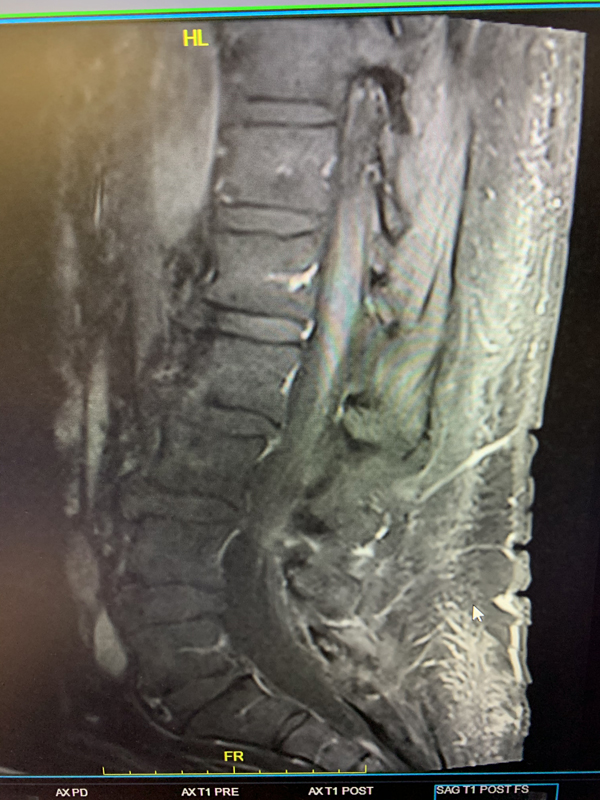

The patient is a 65-year-old woman with a history of hypertension and hypercholesterolemia who was experiencing bilateral lower extremity weakness and numbness for close to one year in addition to some urinary incontinence for the preceding 6 months. The patient ultimately saw a neurologist who ordered an MRI of her lumbar sacral region revealing a bright signal within the lower spinal cord on T2-weighted sequences with enhancement and flow voids seen on the dorsal aspect of the spinal cord suggestive of spinal dural arteriovenous fistula (Figure 1). She was referred for a neurovascular consultation. Physical examination was significant for 4/5 weakness on the right hip and leg muscle groups with decreased pinprick and light touch sensation in both lower extremities in a stocking distribution and decreased vibratory sensation in both toes.

(Figure 1) Pre-treatment MRI image of lumbar sacral region.